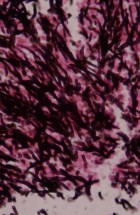

- Детекција тетрациклина у костном ткиву дивљих животиња у циљу контроле оралне вакцинације дивљих животиња;